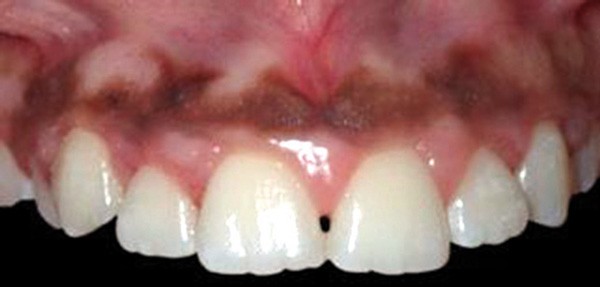

L’omnipraticien est très souvent confronté à cette question lors de sa pratique quotidienne : quel est le bon moment pour adresser les enfants chez l’orthodontiste ? La réponse peut recéler quelques difficultés, car elle est spécifique à chaque enfant. Le temps où il était conseillé d’attendre la denture définitive pour intervenir est révolu : certaines interventions précoces permettent aujourd’hui dans certains cas de raccourcir et de simplifier les traitements orthodontiques. C’est notamment le cas des anomalies transversales, qui sont celles qui sont traitées le plus précocement, dès 6 ans. Ainsi, lors d’anomalie cliniquement évidente, la consultation orthodontique s’impose. Cependant, certaines anomalies sont plus discrètes, et donc plus difficiles à dépister. Une panoramique doit toujours être réalisée en première intention afin de dépister les agénésies. Puis, même en l’absence d’anomalie évidente, il est recommandé d’adresser les enfants chez l’orthodontiste entre 7 et 9 ans : celui-ci sera ainsi à même d’adapter la prise en charge, et surtout l’âge idéal de prise en charge pour chaque patient(fig. 3 et 4).